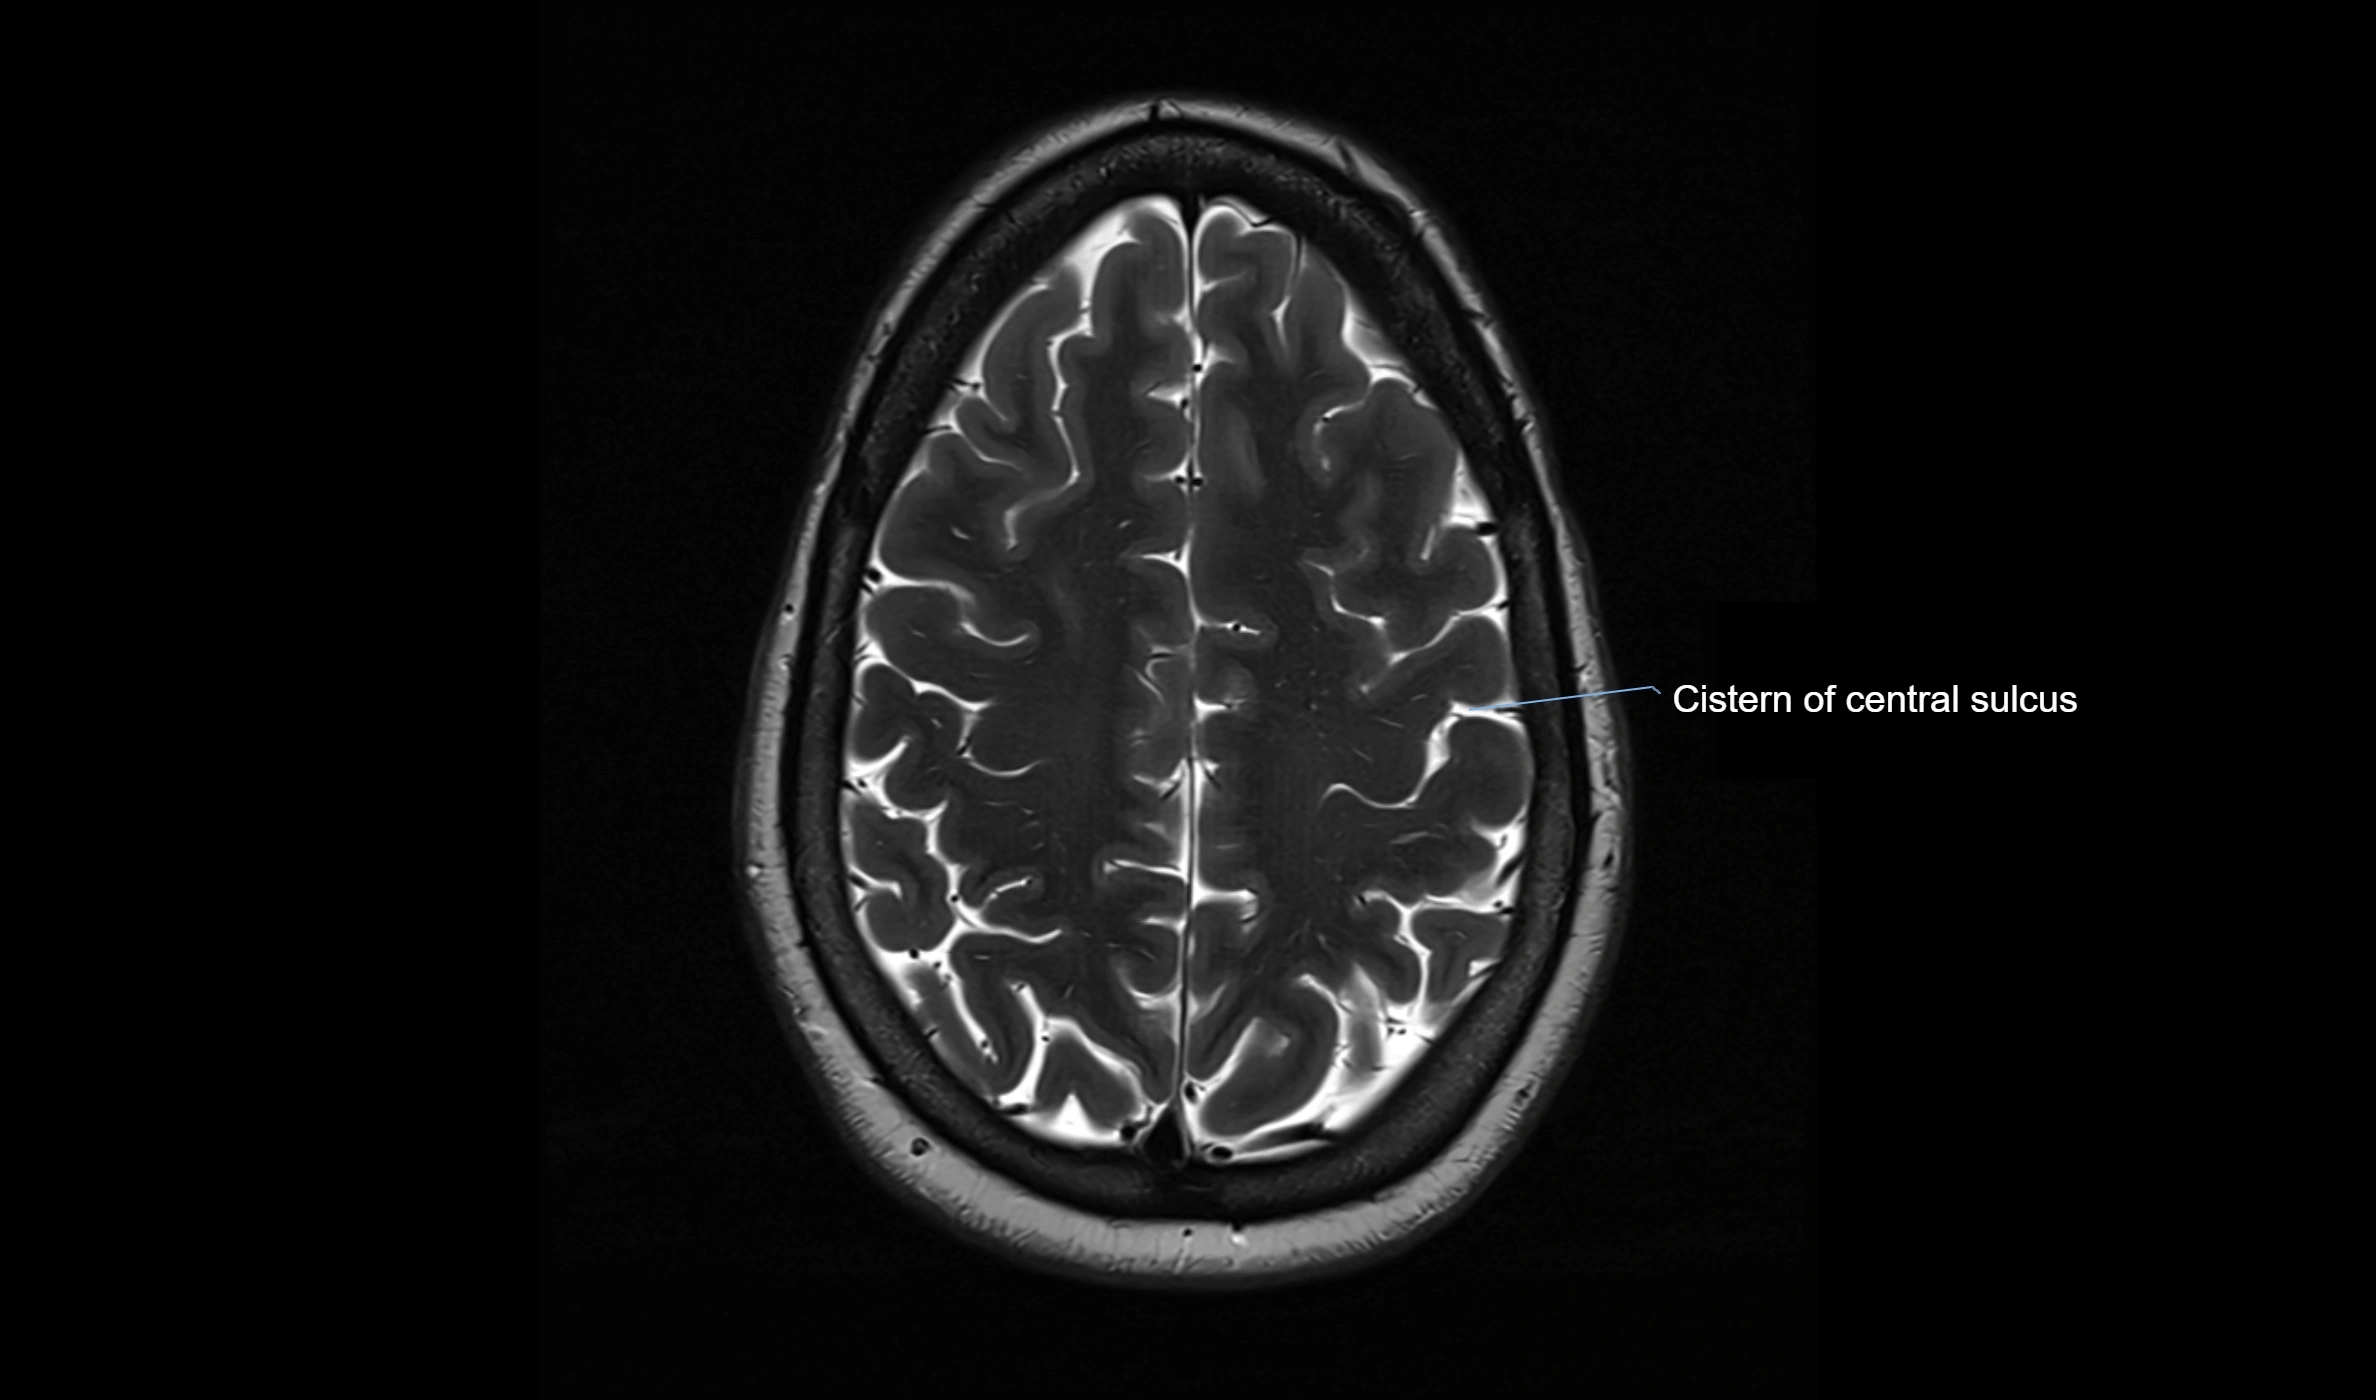

MRI images

image